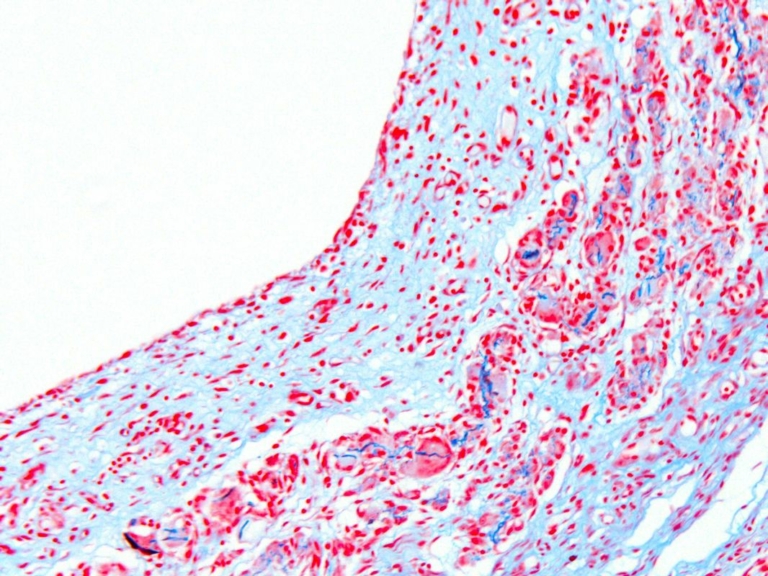

Skin; Picrosirius red stain